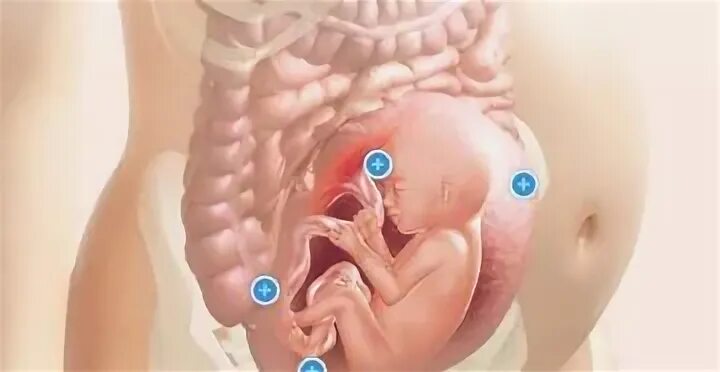

20 недель часто шевелится